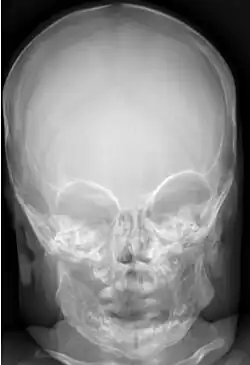

Im Röntgenbild findet sich umschrieben in der betroffenen Region eine massive Kortikalisverdickung durch periostale Apposition. In der Kernspintomographie kann die Ausdehnung der Entzündungsreaktion in den angrenzenden Weichteilen und im Knochenmark nachgewiesen werden. Blutuntersuchungen können abnormal hohe Werte für Alkalische Phosphatase, C-reaktives Protein und Immunglobulin sowie eine beschleunigte Blutsenkungsreaktion und eine Leukozytose ergeben.[15]